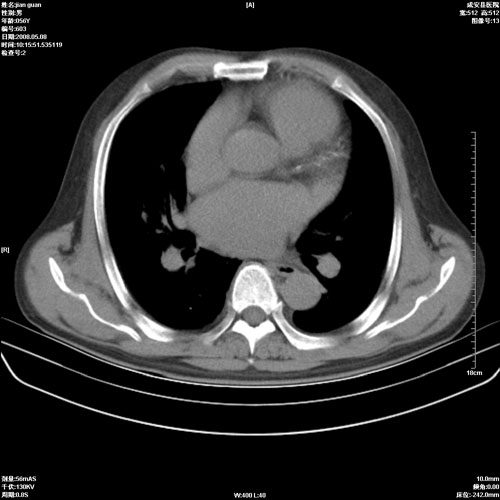

病人 男 60岁 主诉 胸闷 无明显发热 一般情况尚可。

考虑1心功不全,肺水肿

2.心脏增大(以左心室增大为著),请结合b超及听诊.

2.肺门血管扩张,心脏增大,为肺心病

3.肺心病.

陈旧性肺结核,左心房扩大,左心衰竭

2右上肺结核纤维性病灶、肺气肿 ,肺心病